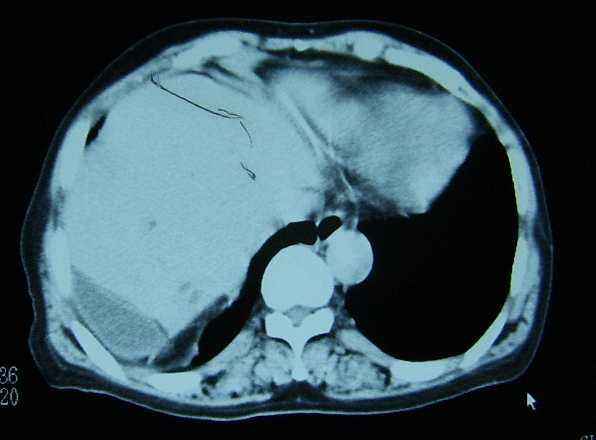

标题: CL0653:【】异位胆囊 [打印本页]

标题: CL0653:【】异位胆囊

女56y右上腹不适数年.

异位胆囊